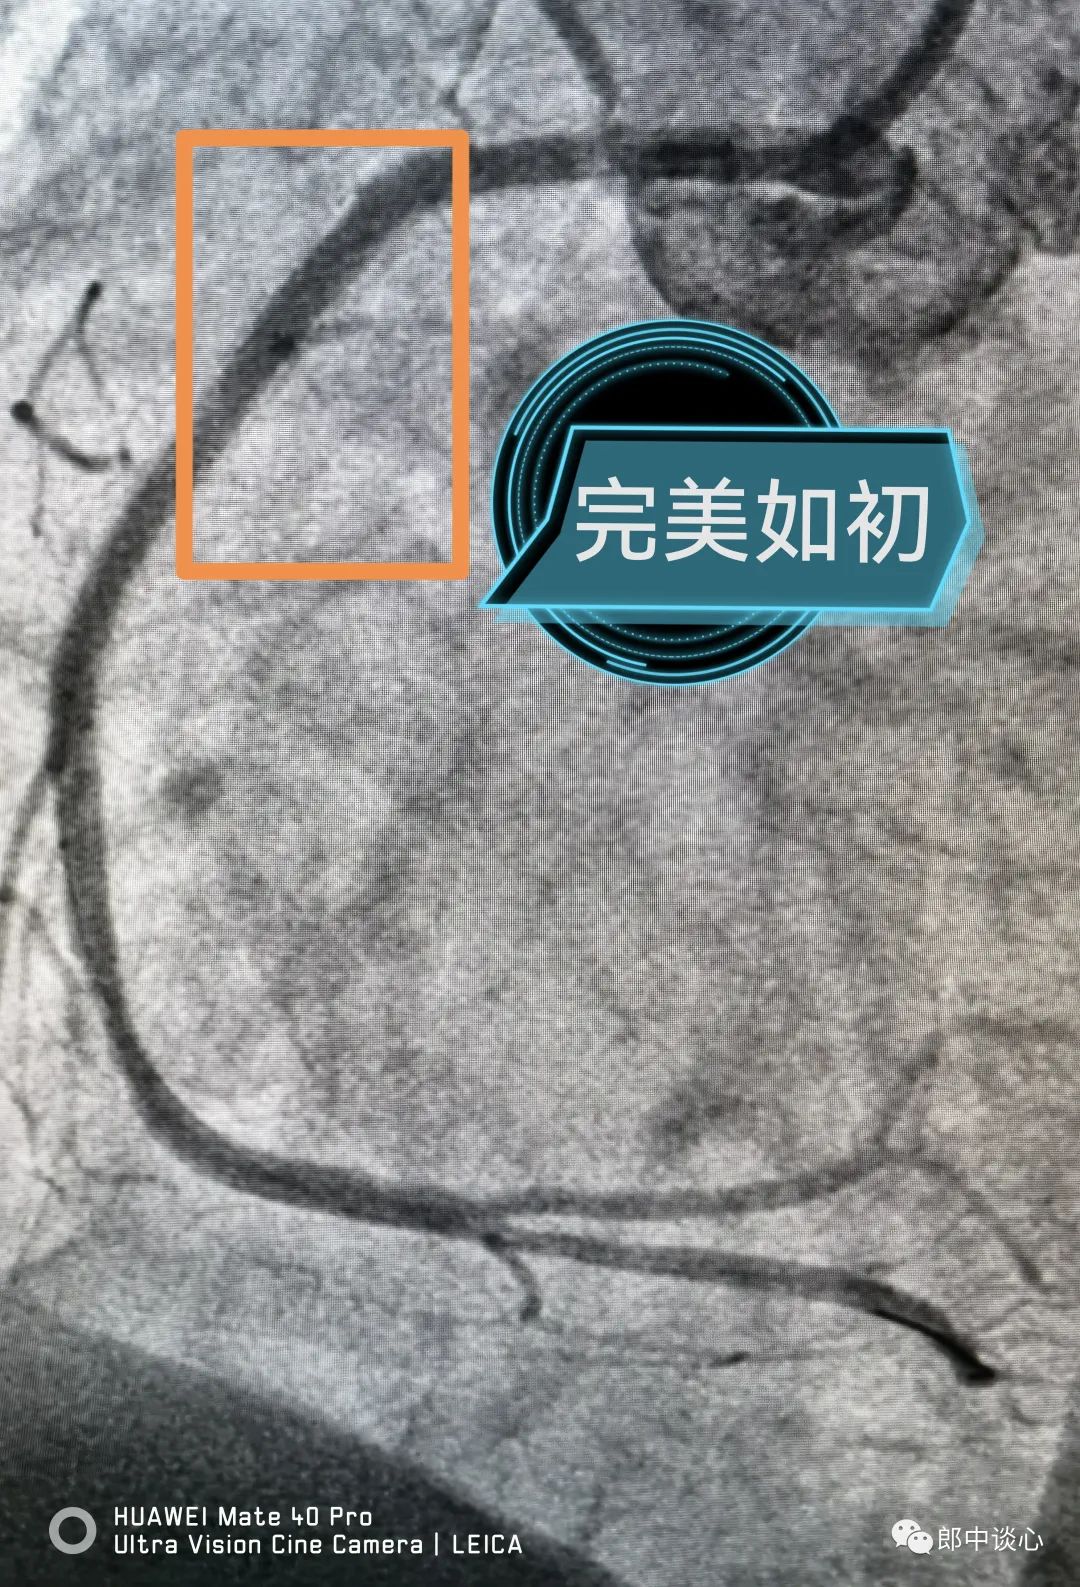

前降支和回旋支完全血运重建后的冠脉似乎又完美如初了!这位病友最值得称道的地方是在一般体检后发现问题,没有不加重视地放过,进一步心脏体检结果发现了问题,并完美解决了问题。